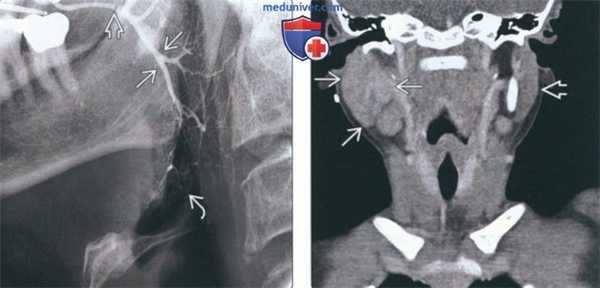

(Слева) На кадрированной панорамной рентгенограмме в правой околоушной железе визуализируются множественные сиалолиты различного размера, которые необходимо дифференцировать с кальцинатами в небной миндалине и обызвествленными лимфоузлами. Последние обычно имеют неправильную форму и напоминают цветную капусту. Относительно часто встречаются множественные сиалолиты.

(Справа) На кадрированной аксиальной КЛКТ визуализируется сиалолит в задних отделах паренхимы правой околоушной железы. Примерно 17% сиалолитов околоушной железы расположены интрапаренхиматозно. (Слева) На обработанной традиционной сиалограмме визуализируется минимально обызвествленный сиалолит(муцинозная бляшка) в протоке Стенсена, выглядящая как дефект наполнения. Участки расширения протока перемежаются со стриктурами, что свидетельствует о сиалодохите.

(Справа) На КТ с КУ в аксиальной плоскости определяются типичные признаки острого паротита в виде интенсивного накопления контраста в сочетании с сиалолитом (протоковым конкрементом) в в дистальном сегменте протока Стенсена. Определяется также уплотнение вышележащей платизмы и подкожного жира, соотносящееся с острым воспалительным процессом.

(Справа) На кадрированной аксиальной КЛКТ визуализируется сиалолит в задних отделах паренхимы правой околоушной железы. Примерно 17% сиалолитов околоушной железы расположены интрапаренхиматозно.

(Слева) На обработанной традиционной сиалограмме визуализируется минимально обызвествленный сиалолит(муцинозная бляшка) в протоке Стенсена, выглядящая как дефект наполнения. Участки расширения протока перемежаются со стриктурами, что свидетельствует о сиалодохите.